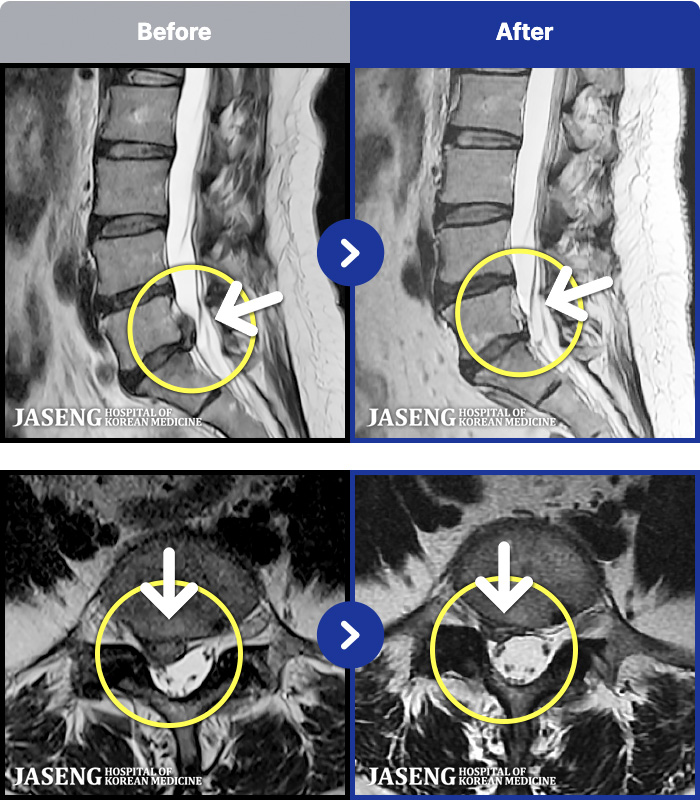

[õ_ũ] ڰ Ͼ ؽ İ Ϻ

No.99

ȸ 803

[õ_㸮ũ] 㸮 , ٷϰ ־.

No.98

ȸ 717

[õ_㸮ũ] 㸮 , кο ٸ ־.

No.97

ȸ 720

[õ_㸮ũ] 㸮 , ٸ ־.

No.96

ȸ 809